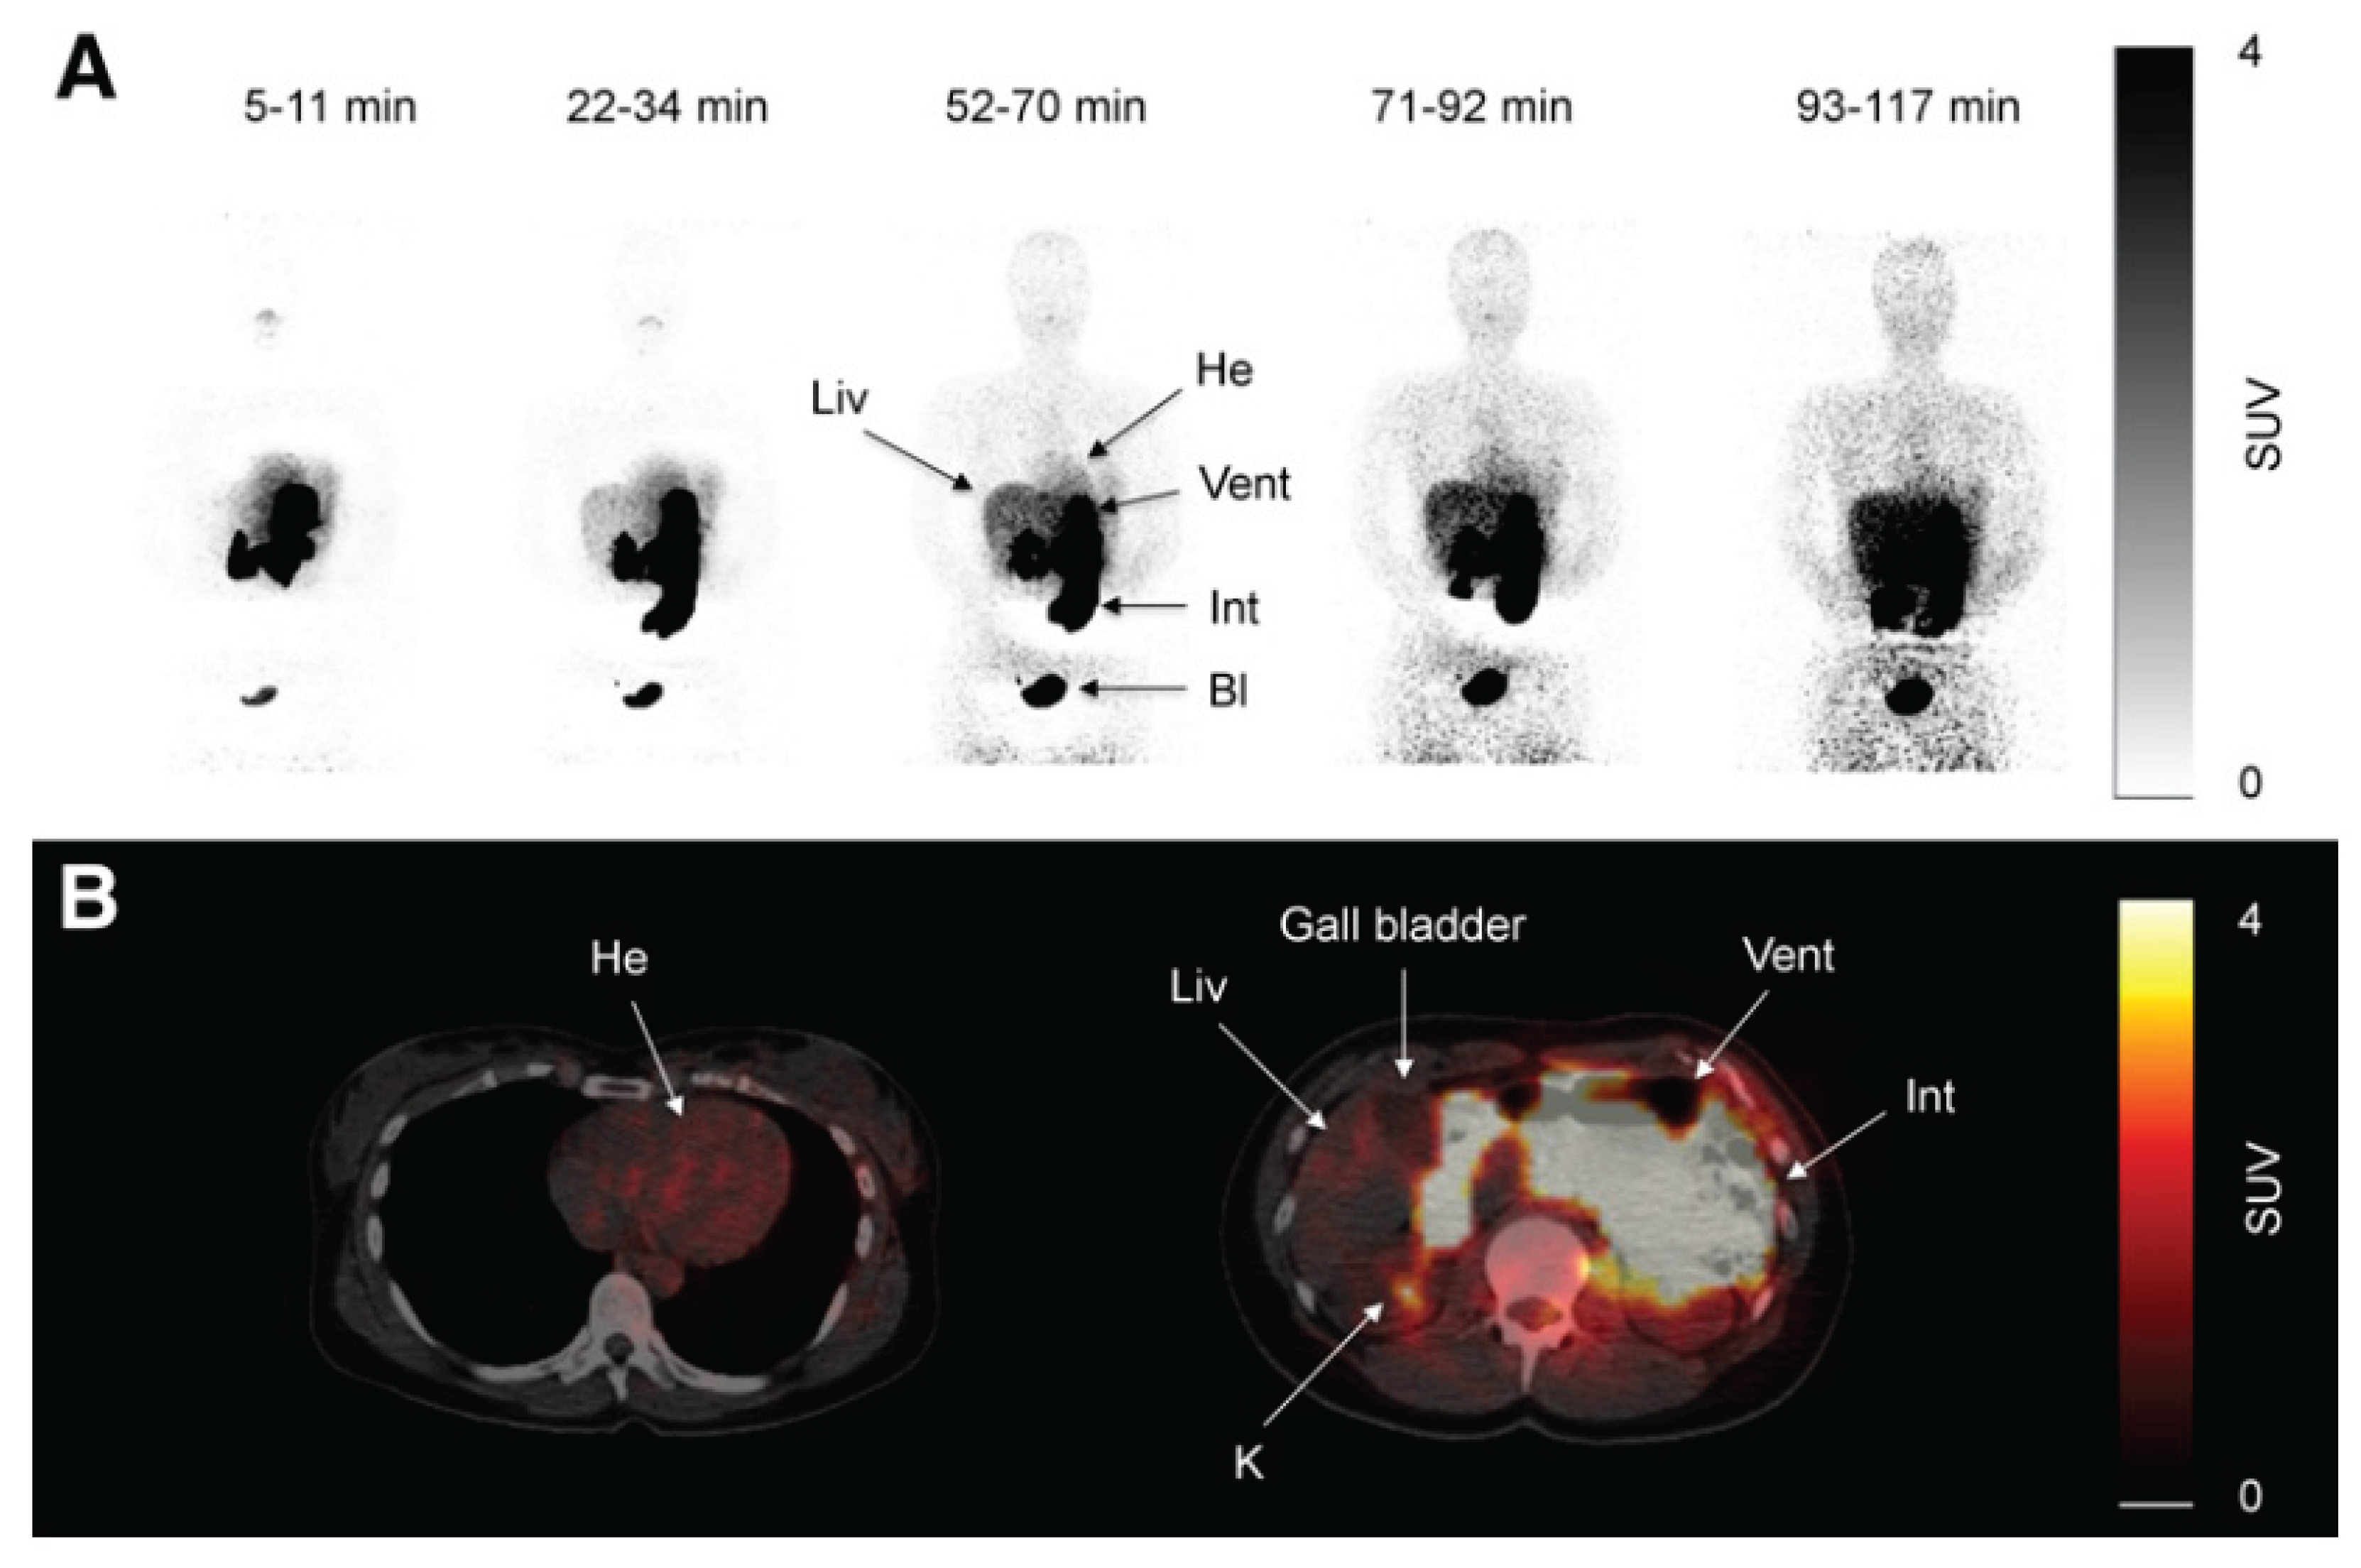

C11-metformin (9.5 microSv/MBq=ca.1.1 micrograms), first injected intravenously, allowed to study its biodistribution in humans, by the PET-scan technique [153]. Most of the activity was found in the liver, the kidney and the urinary bladder. Activity peaked immediately after injection and most of the compound was cleared from the blood 20 minutes after injection. In the kidney there was quick intense activity (80% of the injected activity) with an equally rapid decrease with a reversibility velocity like that of the liver but faster. In the liver the peak of the activity was of course lower (15% of that in the kidney) because of the much larger volume of the cellular distribution (Figure 1 upper panel).

After rapid ingestion of the strong basic compound C11-metformin (18.1micro Sv/MBq, half-life= 20.4 minutes) dissolved in water containing 100mM (NH4)2-HPO4 [pH=5], consecutive whole-body scans were performed. Dosimetry calculations were performed for the stomach content, small intestine, liver, kidney and bladder content. It was demonstrated that hepatic metformin uptake is very rapid and fully reversible, but the accumulation of the activity is higher than after intravenous administration, as, although slower, the tracer delivery comes from the portal blood through the liver first. Two hours after the oral ingestion of the tracer the bulk of the radioactivity is still to be found in the intestine (Figure 1 lower panel) and no further observation of the fate of the radioactive metformin was possible.

The kidney to blood activity ratio was identical independently of the administration route of the radioactive metformin. Some discrete uptake of the tracer was found in the salivary glands and discrete uptake was found also in the intestine. No activity was found in the gallbladder. Significant amounts of the tracer passed to the small intestine 10 minutes after ingestion.